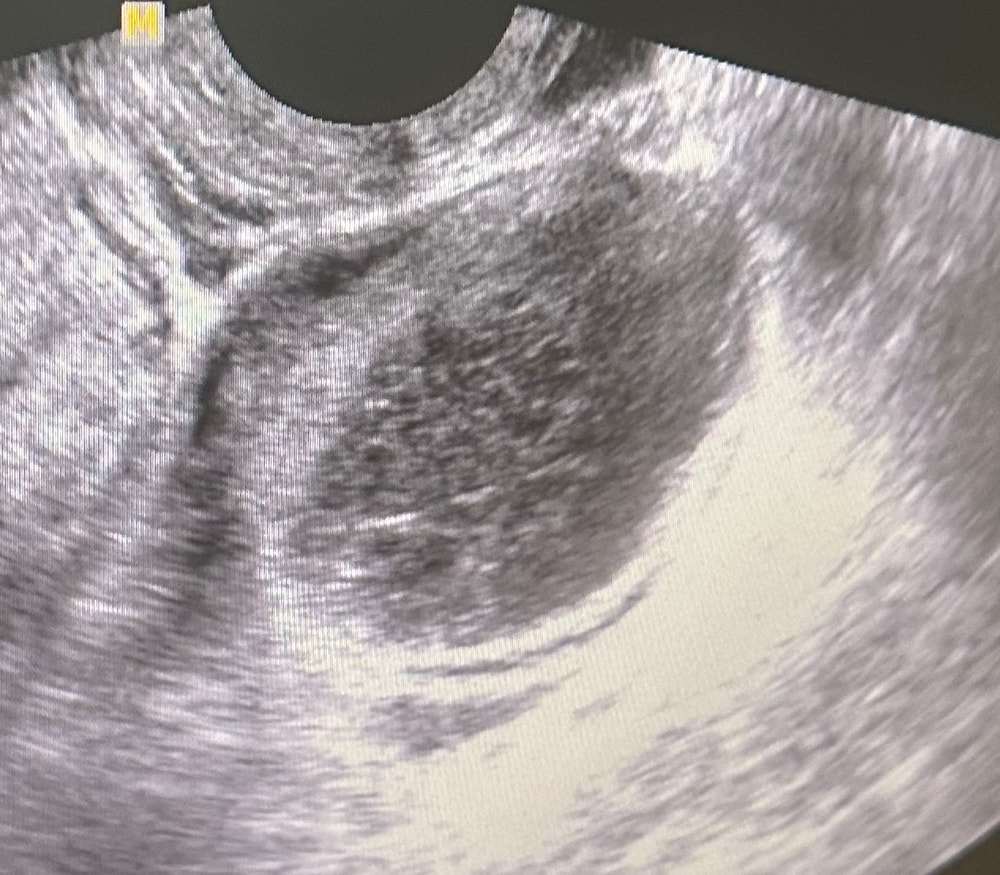

На эндометриоидную. Дисперсное содержимое характерного вида

Ольга, если честно сомневаюсь что это именно эндометриоидная киста , не похоже на кисту желтого тела ?

Лиана, может узи такое не очень, но жт несколько более контрастно выглядит, а не таким серым содержимым. Их дифференцируют при сомнениях тупым наблюдение пару циклов: если уменьшается, значит не эндометриома ))